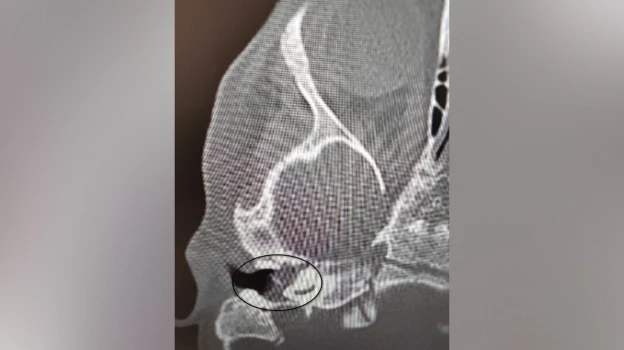

Врачи Воронежской областной детской клинической больницы №1 (ВОДКБ №1) вылечили редкое заболевание у двухлетней пациентки и смогли сохранить ее слух. У ребенка был правосторонний хронический гнойный средний отит и подозрение на врожденную холестеатому барабанной полости (кистозное патологическое образование в среднем ухе. – Прим. ред.). Это заболевание встречается особенно редко в таком раннем возрасте. Из-за холестеатомы девочка могла потерять слух. Об этом сообщили в пресс-службе министерства здравоохранения Воронежской области в среду, 5 ноября.

После ОРВИ у ребенка появилась боль в ухе. Консервативное лечение не принесло результатов, ситуация осложнилась парезом лицевого нерва – слабостью мимических мышц. Врачи приняли решение о хирургическом лечении. Заведующий оториноларингологическим хирургическим отделением Антон Мащенко провел сложную операцию, под контролем операционного микроскопа он удалил холестеатому, провел декомпрессию лицевого нерва и восстановил механизм звукопроведения.